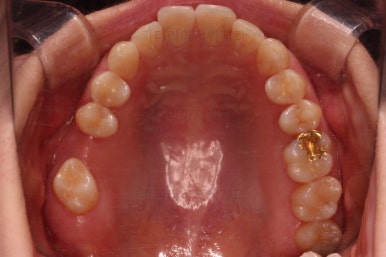

마찬가지로 부산치아교정비용 초진 시 입안의 모습입니다.

아랫니가 많이 보이지 않는 타입이라서 잘 몰랐는데 입안을 관찰해 보니 아래 앞니가 삐뚤어 있네요.

이 부분도 꼭 교정해야 될 정도는 아니여서 선택의 문제라고 할 수 있는데요.

어금니가 문제였습니다.

윗니 어금니가 하나 없는 상태였고요.

어금니가 없이 지낸지 꽤 시간이 흐른터라 뒤쪽 어금니가 앞으로 쓰러져 공간을 잠식하고 있었습니다.

이번 환자분이 선택한 앞니 부분교정 장치는 MTA라는 장치인데요.

부분교정에 좀 더 특화된 부피가 작고 심미적인 장치입니다.

물론 철사는 들어가고요.

어금니쪽은 쓰러진 어금니를 원위치 시키기 위해서 미니스크류를 식립하여 준비작업을 해줍니다.